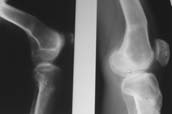

Пациент В. 53 лет, травма в феврале 2009. ДЗ. Открытый оскольчатый перелом нижней трети голени. При боли поступлении выполено ПХО, аппарат Илизарова. В последующем проводили ВХО, резекция костных отломков, укорочение 6 см, рана зажила. Была выполнена остеотомия большеберцовой кости в проксимальном отделе, резекция. Производилось тракция. На последних рентгенограммах выявлено, что одновременно с "выращиванием" регенерата произошло низведение надколенника на длину выращенного регенерата. Клинически: активное разгибание сохранено, объем движений в колене 180-110 градусов. Черными стрелками обозначен верхний край надколенника с одной и с другой стороны. Красная стрелка обозначает пальпируемую связку надколенника. Причина - остеотомия выше места прикрепления связки надколенника. Вопрос: была ли у кого подобная ситуация? Что делать? При первом обдумывании приходит решение: отсечение места прикрепления связки надколенника с костным блоком, перемещение на "правильное" место, укорочение сухожилия четырехглавой мышцы.

По снимкам - плотность регенерата хорошая, сложностей с фиксацией в него костного "основания" быть не должно.

К сожалению, подобное осложнение "нет-нет да и возникает" при удлинении, коррекции деформации голени. В англоязычной литературе оно описано как "patella baja". Один из вариантов лечения - проксимальное перемещение надколенника приемами чрескостного остеосинтеза.

По-моему, надколенник низвелся на величину, гораздо меньшую удлинению.

Я бы уменьшил диастаз между фрагментами сантиметра на два. Судя по снимкам, регенерат это может позволить.